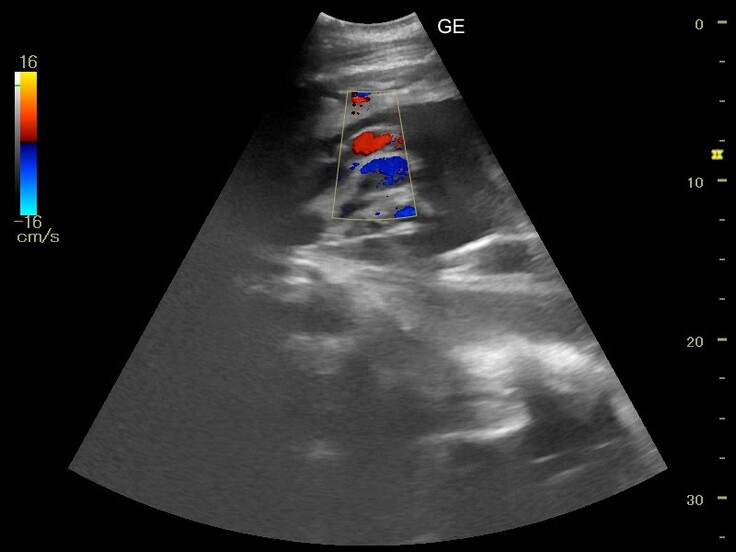

詳しくみてみたところ、へその緒の中にちゃんと血流があることも確認できました。

この結果から、胎児の心臓はちゃんと動いているだろうということが確認できました。